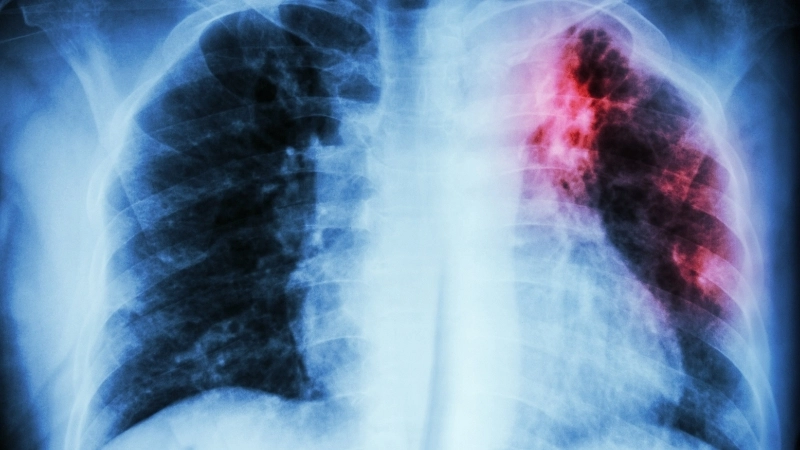

Hình ảnh về bệnh lao thể hiện qua tổn thương đỉnh phổi